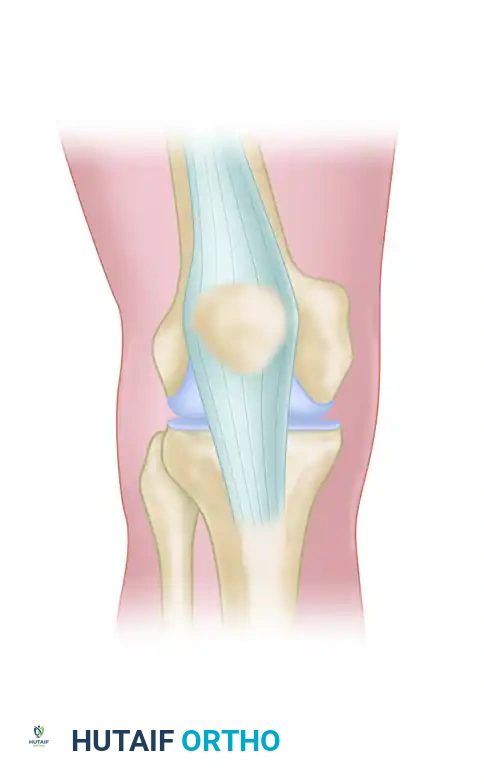

Diagrammatic representation of the Subvastus (Southern) approach, highlighting the elevation of the vastus medialis to expose the medial distal femur.